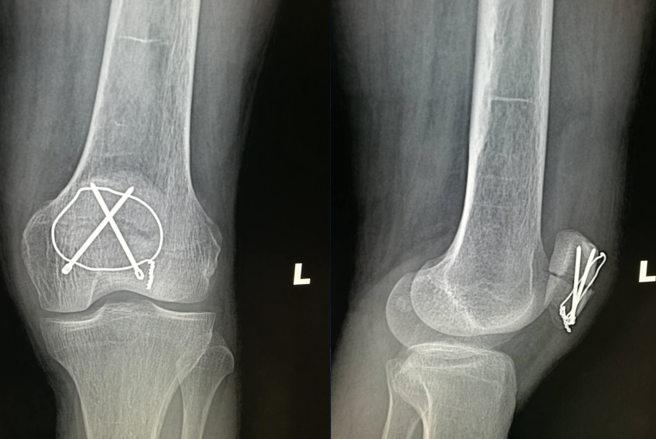

患者,男,60岁

主诉:摔伤致左膝部肿痛,活动受限

查体:左膝部肿胀,压痛,活动受限明显。下肢血运感觉正常,各趾可自主活动。

辅助检查:X片示左髌骨骨折,骨折端分离

诊断:左髌骨骨折(横行骨折)

点氏复位钳经皮复位打入一克氏针临时固定

用电钻在髌骨上下极打一骨洞,用腰穿针带过钢丝

紧贴钢丝上方打入两髌骨针

折断髌骨针后再次收紧钢丝

术后复查